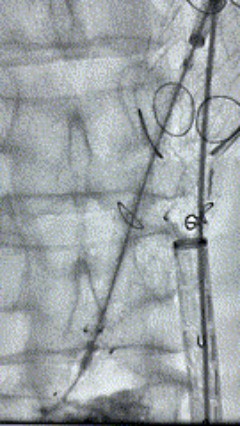

7. 经长鞘重新选入左侧外分支,并超选进左肾动脉,沿导丝送入外周血管覆膜支架7*60mm一枚,并予以球囊后扩张,手推造影显影良好。

8. 从右侧股动脉入路送入腹主支架AB-24-12-110-S,近端重叠胸腹主动脉支架远端,调整好支架位置后释放。

9. 经左股动脉送入导丝导管,超选进腹主动脉支架短腿内,后沿导丝送入髂支,同理,右侧沿导丝送入髂支并释放,使用先健顺应性球囊后扩各支架连接处及支架近远端,最后通过预留导管向瘤腔注入人纤维蛋白粘合剂数支,造影显示分支通畅。